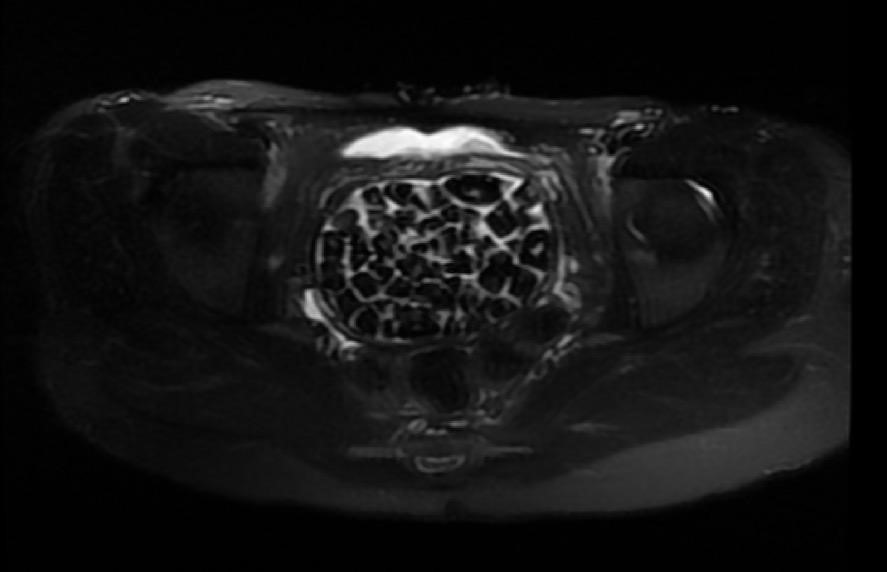

Hastasının durumuna yönelik konuşan Üroloji Uzmanı Doç. Dr. Erkan Erkan, "Hastamızın 2004 yılında doğduğunu ardından doğar doğmaz ekstrofi vezika dediğimiz 50 binde bir görülen bir anomaliden dolayı art arda ameliyatlar geçirdiğini öğrendik. 10 yaşında yine bir ameliyat geçirmişti, gerekli görüntüleme ve tetkiklerimizi yaptırdık. Normalde mesanesinin olması gereken yerin hemen arka kısmında taşlarla dolu bir kese olduğunu gördük, bunun üzerine ek görüntülemeler; MR çektirdik. Hastamız çelişkili açıklamalar almıştı, kendi radyolojik kliniğimiz ve edindiğimiz konsültasyonlarda taşların mesanede değil vajinal boşlukta oluştuğunu düşündük, bir planlama yaptık. Kadın doğum hocamızın da çabasıyla taşları tamamen temizledik ardından ileride normal bir hayat sürmesi bakımından oraya plastik cerrahi yaptık. 287 adet taş çıkardık, pratikte gerçekten görünce çok şaşırdık çünkü bu aynı zamanda literatürde çok nadir görülen bir olay. Biz ameliyata hazırlanırken de teorik olarak biraz araştırdık. Literatürde gördüğümüz kadarıyla buna benzer bu tanıma uyan bir vaka vardı. Literatürde sanırım yayınlanmış 2’nci vaka olacak. Farkındalık çok önemli, bilinçli bir hastamız vardı. Doğumsal anomaliyle doğan çocuklarımızda ileride bunlara bağlı bazı sıkıntılar çıkabileceğinin öngörülmesi lazım. İlgili tedavilerini alsalar bile düzenli takiplere gelmeleri gerekiyor. İleride eğer dikkat etmezse ki zannetmiyorum, tekrarlayabilir. Bu rahatsızlık ekstrofi vezikal epispadias durumu çok nadir bir durum" dedi.

"Tüm vajenin taşlarla dolu olduğunu gördük"Genç kızın uzun süredir devam eden karın ağrısı olduğunu söyleyerek sözlerine başlayan Jinekolojik Onkoloji Uzmanı Op. Dr. Emin Erhan Dönmez, "Mesane taşları olduğu düşünülerek daha büyük bir hastaneye refere edilmiş. Aramızda mini bir konsey yaparak muayene ettik. Vajen bir hazne görevi görerek orada durağan bir idrar, uzun süre beklediği için idrar içindeki minerallerde çökerek taşlar oluşmuş. Mesanedeki idrarın vajene akmış olabileceği ve vajende göllenen idrar nedeniyle taşların burada oluşacağını düşündük, ameliyatımızı planladık. Ameliyata tanı amaçlı girmiştik, sistoskopi (Mesane gibi idrar yollarını kapsayan kısımlardaki rahatsızlıkların teşhis ve tedavisinde kullanılan endoskopik bir yöntem) dediğimiz ameliyatı Erkan Hocam ile birlikte gerçekleştirdik. Önce mesaneyi bir görüntüledik, mesane tabanına yaklaşık 2-3 cm’lik bir alandan vajene fistülize olduğunu gördük. Mesaneden vajene geçtiğimiz esnada tüm vajenin taşlarla dolu olduğunu gördük. Tanı amacıyla girdiğimiz ameliyatta her şey de olağan gittiği için tedaviye geçtik. Taşların çıkabileceği kadar bir genişlik sağladık. Daha sonra yaklaşık en büyüğü 2,5 cm boyutlarında olan, irili ufaklı 287 tane taşı ameliyat esnasında çıkarmış olduk. Taşların tekrarlamaması için idrarın göllenmemesi, en azından dışarıya rahatça boşalabilmesi için vajinal rekonstrüksiyonu sağladık. Ameliyatta da herhangi bir problem yaşamadık. Literatürü Erkan Hocam ile birlikte değerlendirmiştik. Primer olarak vajende birikmiş olan bu kadar çok sayıda taşla ilgili bir makale görmedik, rastlamadık" dedi.